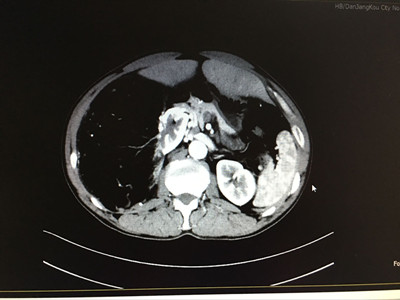

两位患者均为体检时发现后腹腔有一巨大占位,进行详细检查发现肿瘤。据患者介绍,平常并无特别明显症状。其中一名患者为右肾错构瘤,属血管平滑肌脂肪瘤,长25公分,宽16公分,厚13公分,与肝脏、肾动静脉和腔静脉粘连紧密,并将腔静脉挤弯变形、推向左侧。和右肾连在一起有半个足球大小。另一名患者为左肾透明细胞癌,直径21公分左右,囊实性占位病变,与胰腺粘连紧密,肾血管受挤压位置变异。